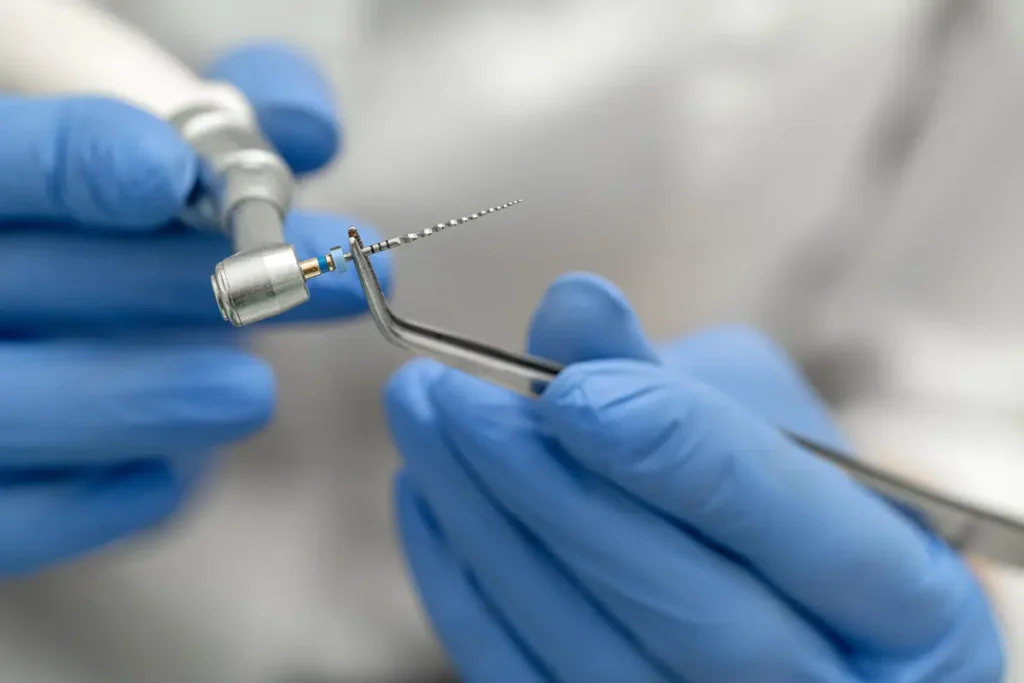

Étape 2 : Création de la Cavité Initiale

Utilisez une fraise boule diamantée ou en carbure de tungstène montée sur turbine. Créez une cavité dont la forme générale correspond à celle de la cavité idéale prévue.

Étape 4 : Suppression du Plafond Pulpaire

C’est l’étape la plus délicate. Utilisez une fraise boule à long col montée sur contre-angle (bague bleue) ou une fraise à pointe mousse (Endo Z® ou Batt).

Équipement et Matériel Recommandé

Fraises Essentielles

Fraise boule diamantée ou tungstène : création de la cavité initiale (montée sur turbine)

Fraise boule long col : suppression du plafond (montée sur contre-angle, bague bleue)

Fraise Endo Z® ou Batt : finition sécurisée avec pointe mousse

Fraise Gates-Glidden : préparation de l’entrée canalaire (optionnel)